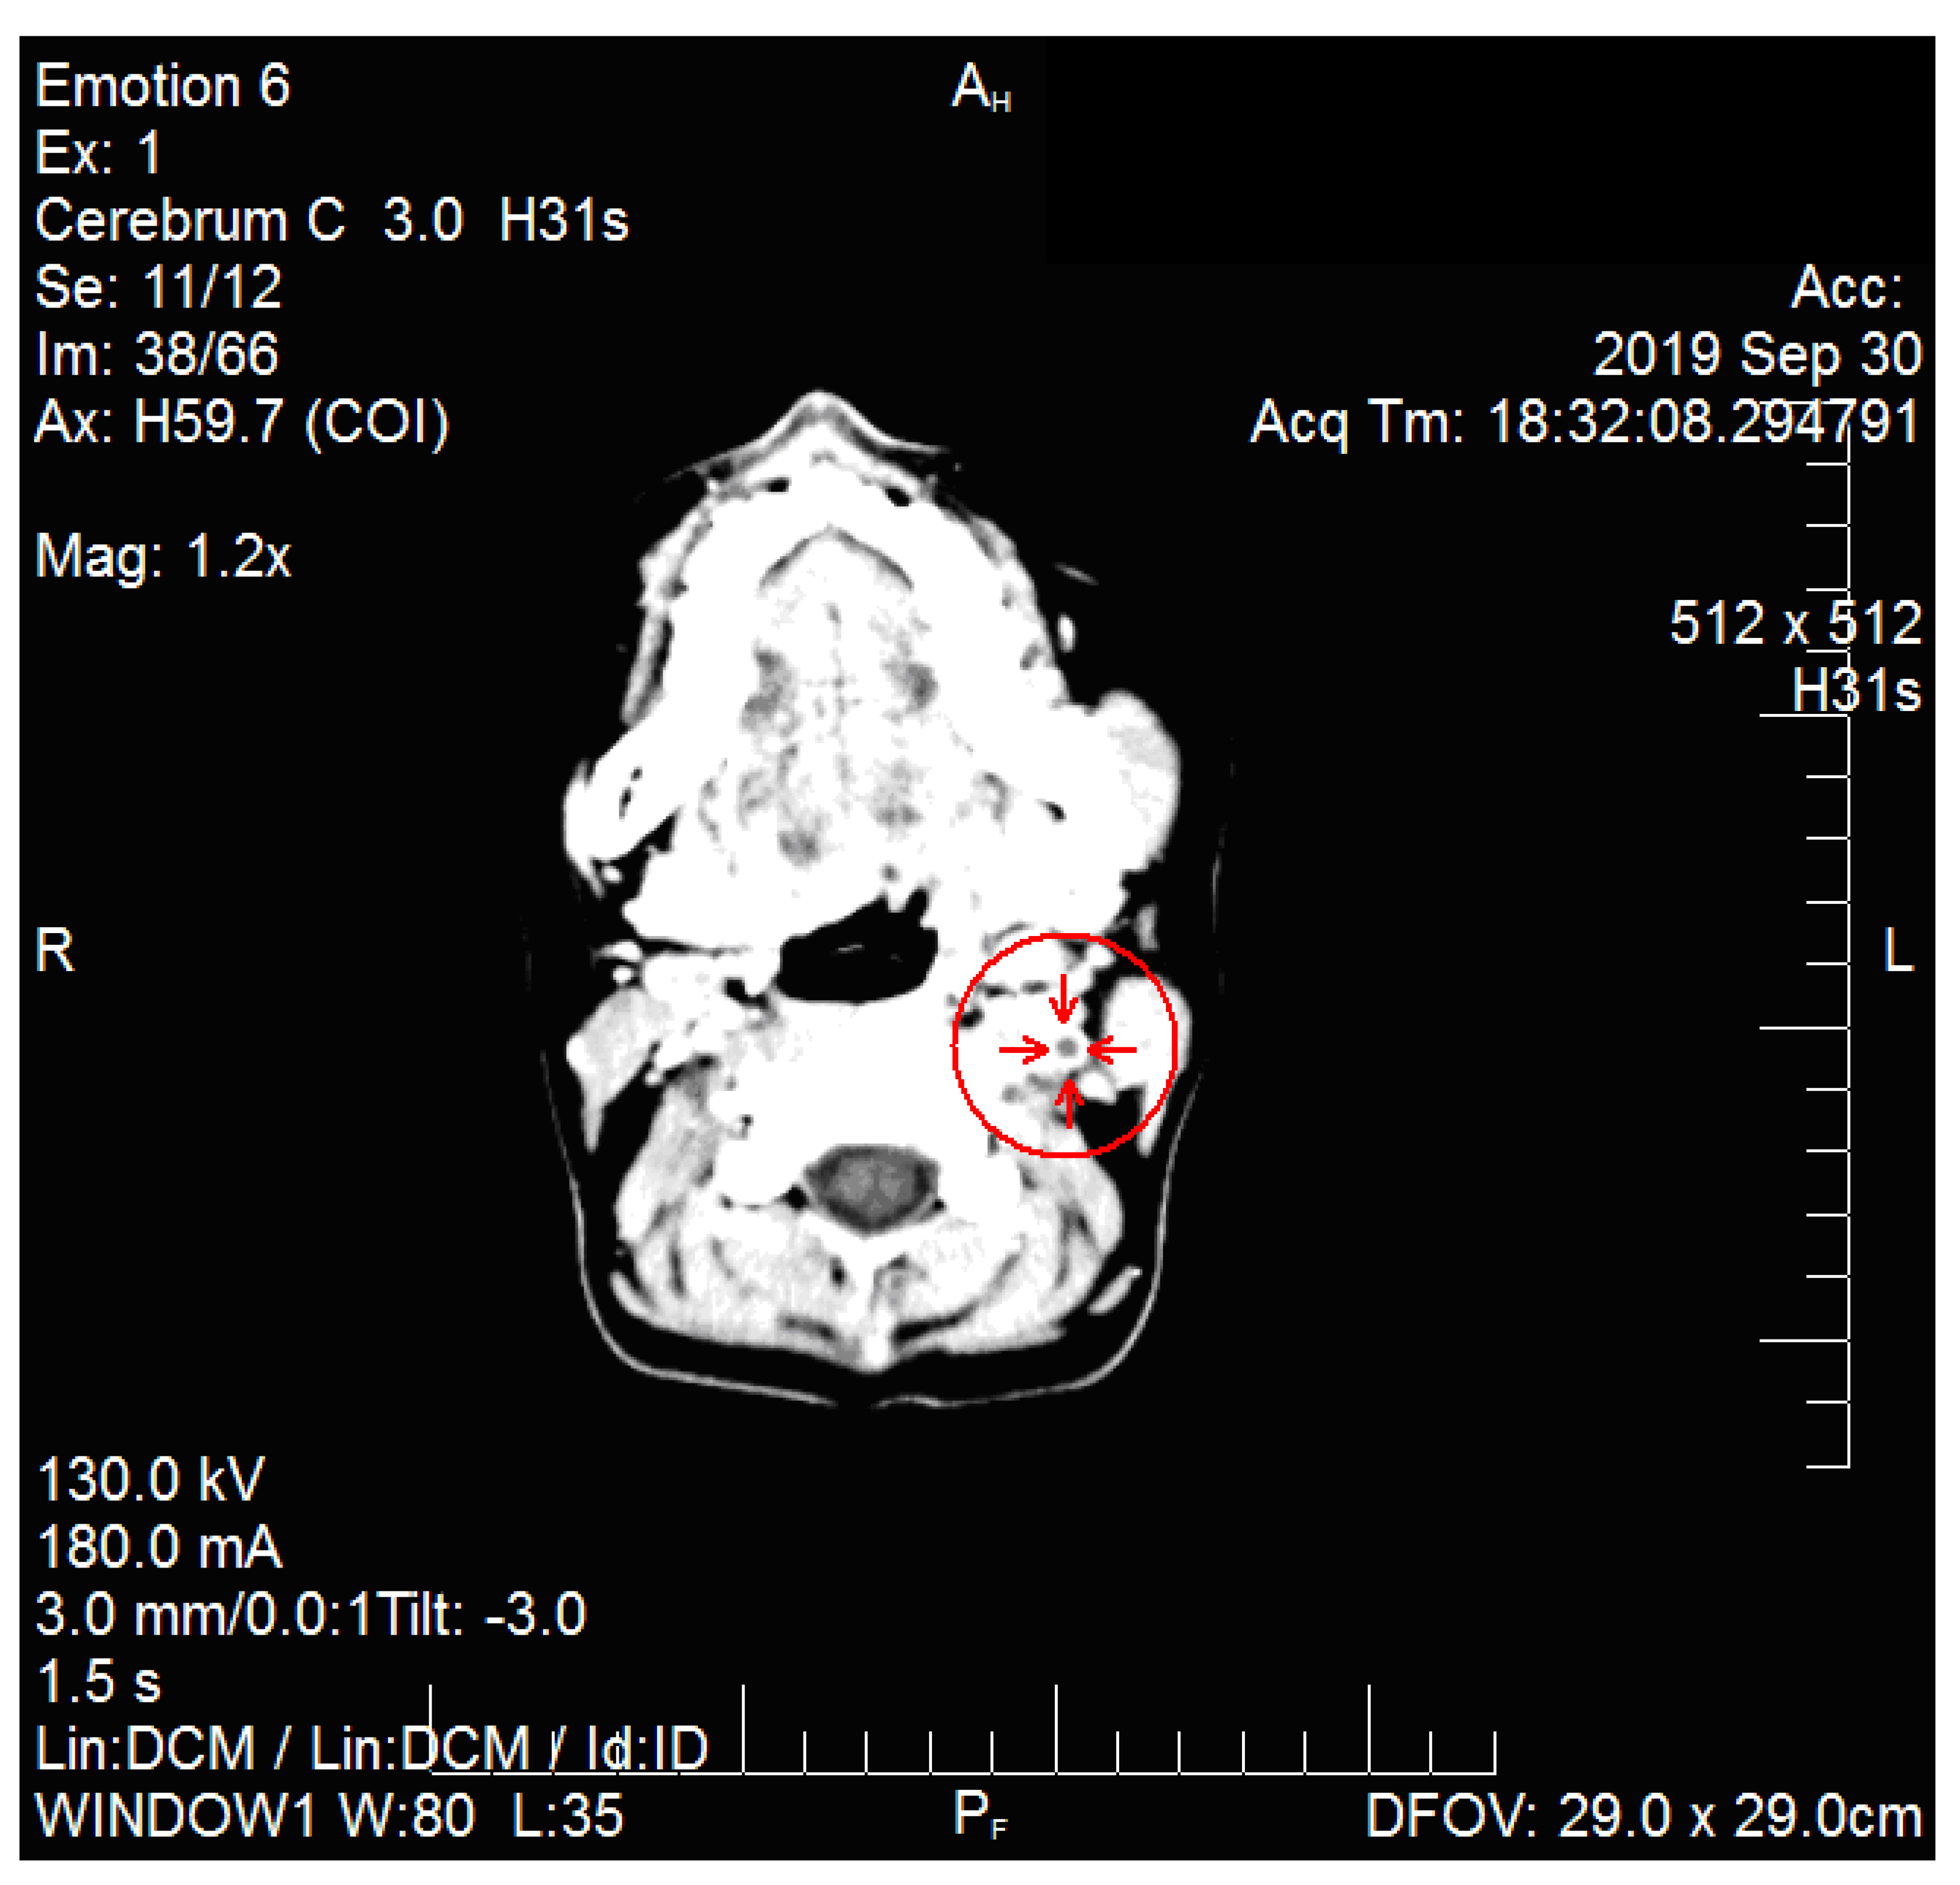

2. Case Report